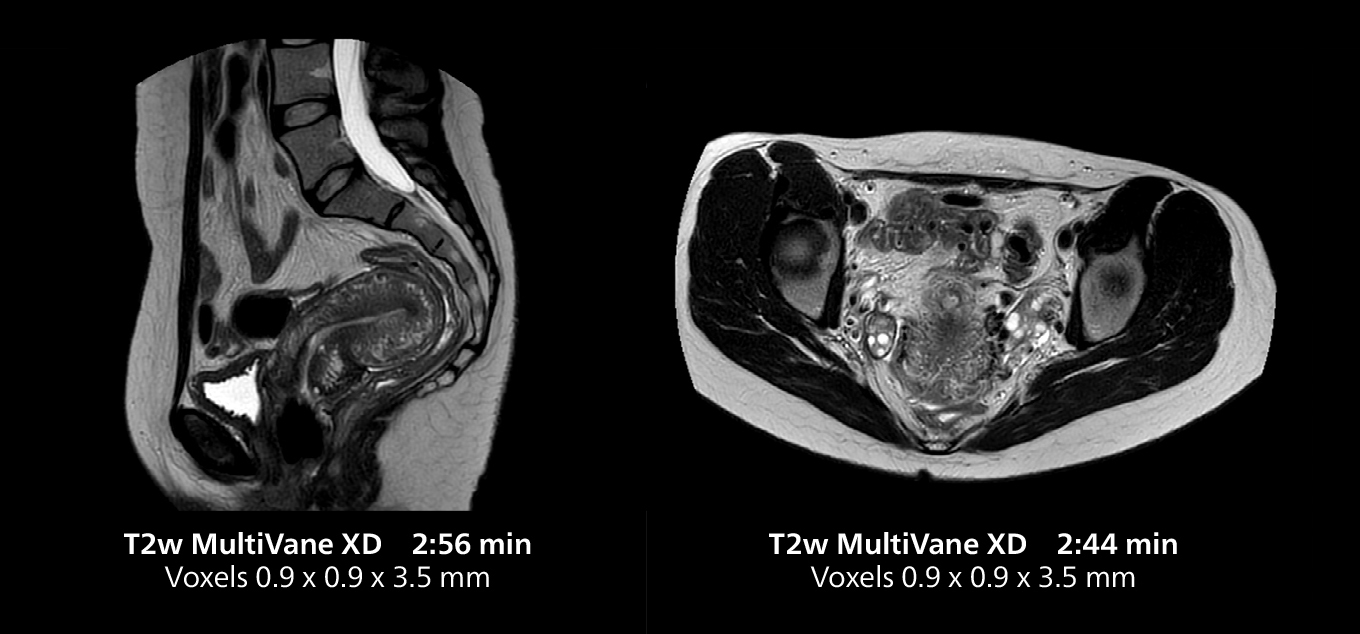

This MRI case illustrates good resolution and imaging quality obtained within reasonable scan times using the MR 5300 1.5T system with the anterior torso cardiac coil that allows use of a large field of view (FOV).